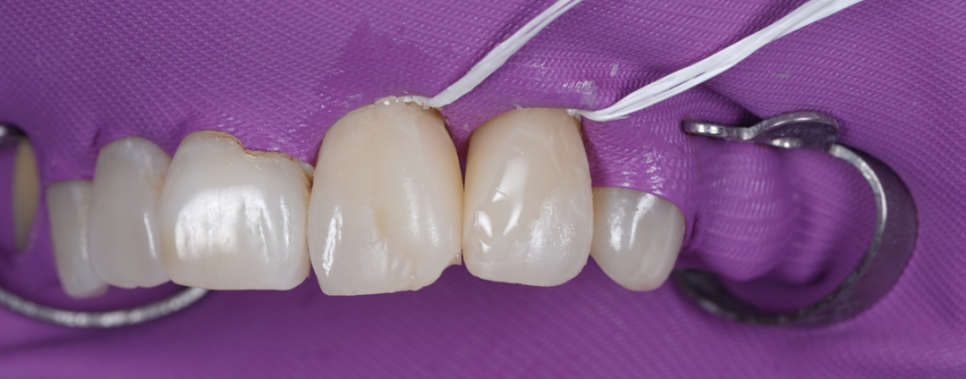

촬영일 : 251230

앞니 사이 공간을 레진으로

꽉 메워둔 상태였어요.

치아 사이는 반드시 치실이 매끄럽게 통과할 수 있는 미세한 틈이 있어야 음식물 찌꺼기가 빠지고 잇몸이 건강하게 유지돼요.

그런데 이걸 꽉 막아버리니 그 안에서 세균이 번식하며 이미 뼈(치조골)가 흡수되는 치주염이 진행되고 있었죠.

한 번에 두껍게 메우는 것이 아니라

아주 얇은 층을 여러 번 쌓아 올려야

자연스러운 빛 반사와 단단한 내구성을

얻을 수 있어요.